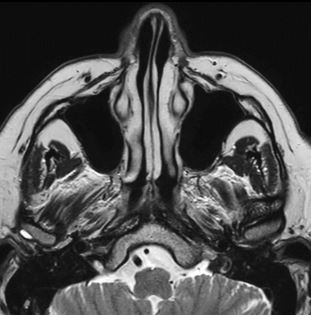

Beispielaufnahmen von einer MRT der Nasennebenhöhlen (NNH)

Die MRT der Nasennebenhöhlen zeigt ihren Mehrwert vor allem in der Diagnostik von akuten oder chronischen Entzündungen sowie in der Früherkennung und Unterscheidung von gut- und bösartigen Tumoren. Auch bei angeborenen Fehlbildungen, bei Verdacht auf Fremdkörper oder zur Operationsvorbereitung liefert sie wertvolle Informationen.

Gerade wenn Beschwerden über einen längeren Zeitraum bestehen und die Ursache unklar ist, ist die NNH-MRT sinnvoll. Die besonders gute Auflösung der Bilder macht die MRT zu einem zuverlässigen Begleiter in der modernen HNO-Diagnostik. Mit den gewonnenen Erkenntnissen können gezielte Behandlungsmaßnahmen eingeleitet oder unnötige Eingriffe vermieden werden.

- Nasennebenhöhlen: Kieferhöhlen, Stirnhöhlen, Siebbeinzellen, Keilbeinhöhlen

- Nasengänge und Nasenmuscheln

- Schleimhäute und deren Zustand

- Nasenscheidewand (z. B. bei Verkrümmungen)

- Weichteilgewebe, Nervenverläufe (z. B. Trigeminusnerv) und Blutgefäße

- Schädelbasis und angrenzende Hirnstrukturen